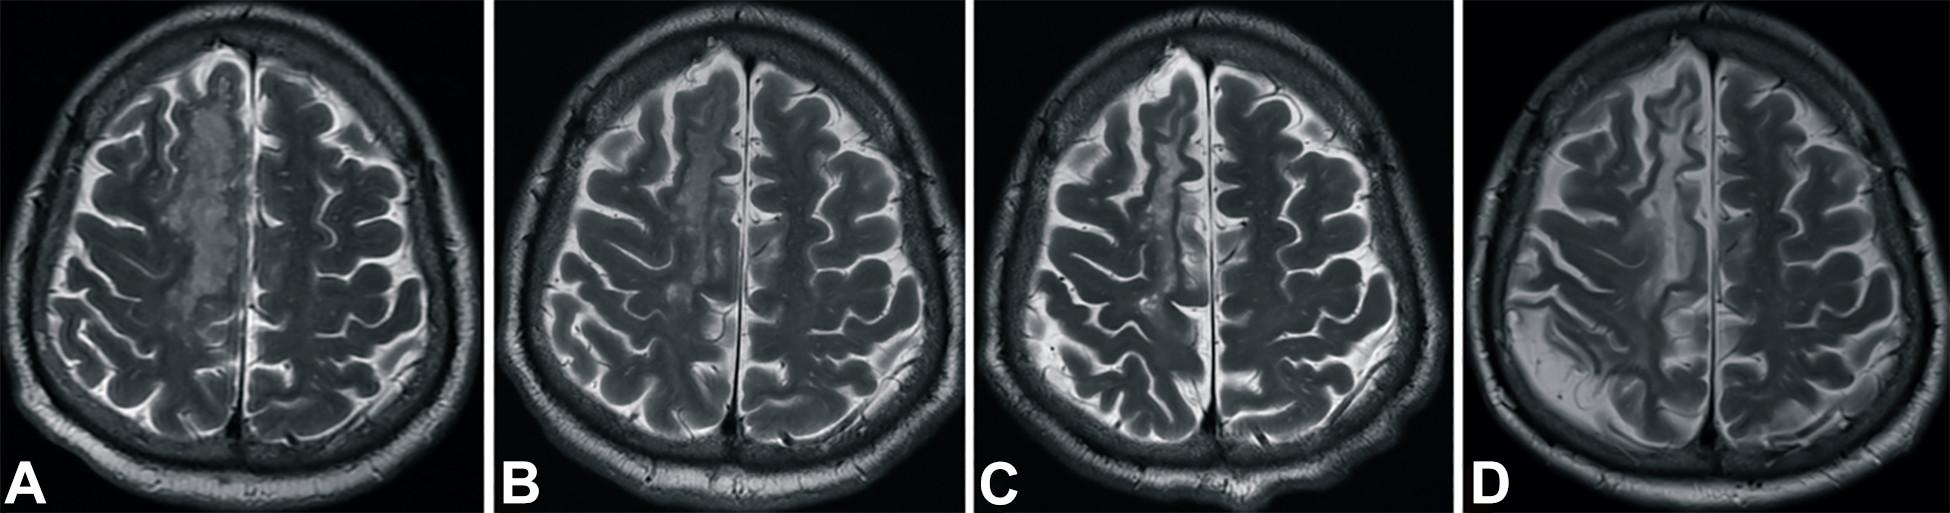

發(fā)病后2小時(shí)和8天行彌散加權(quán)成像(DWI)檢查,發(fā)現(xiàn)右側(cè)放射冠梗塞(白色信號(hào)增加),3個(gè)月后梗塞散在,6個(gè)月后消失(圖2A-D)。

梗塞發(fā)生后2小時(shí)、8 天、3 個(gè)月和 6個(gè)月獲得的T2加權(quán)圖像顯示右側(cè)放射冠白色強(qiáng)度增加(圖3A-D)。